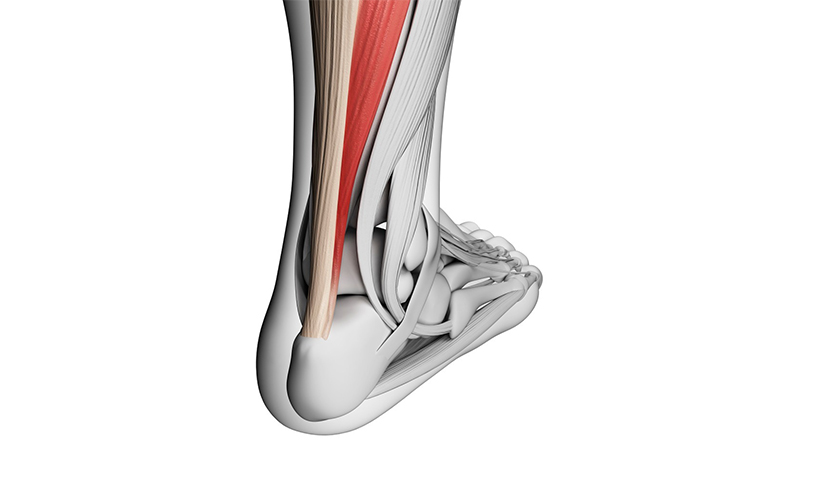

아킬레스파열

우리 몸에서 가장 두껍고 강한 힘줄 중 하나인

아킬레스건에 염증이 생기고 통증과 부종이 발생하는 질환을 뜻합니다.

아킬레스 파열은 장딴지 근육을 발꿈치 뼈에 연결하는 힘줄이인 아킬레스 건이

끊어지는 것을 의미하기에 아킬레스 건염이 더 심화되지 않도록,

조기에 치료를 받아주셔야 합니다.